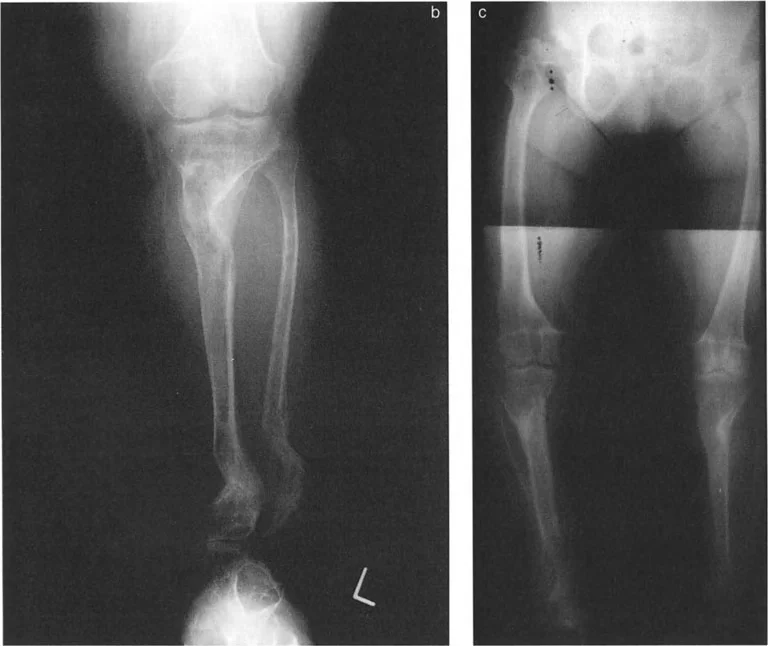

تُعد الإصابات الرضحية (Traumatic injuries) السبب الأكثر شيوعًا لتشوهات قصبة الساق البعيدة لدى البالغين.

* الكسور غير الملتئمة أو الملتئمة بشكل خاطئ: إذا لم يتم علاج كسر في الجزء السفلي من قصبة الساق أو الكاحل بشكل صحيح، أو إذا حدث التئام للعظم في وضع غير طبيعي، فقد يؤدي ذلك إلى تشوه دائم. على سبيل المثال، كسر في الكاحل يلتئم مع تقوس (Varus) أو روحبة (Valgus) في قصبة الساق يمكن أن يغير ميكانيكا الكاحل بشكل جذري.

* الأشعة السينية (X-rays) الواقفة لكامل الطرف السفلي: هذه الأشعة ضرورية لتقييم المحاذاة الكلية للطرف السفلي تحت تأثير وزن الجسم. يطلب الأستاذ الدكتور محمد هطيف صورًا شعاعية كاملة الطول للساق أثناء الوقوف (Full-length standing alignment films) لتقييم المحور الميكانيكي للساق وتحديد زوايا المفاصل بدقة.

* الأشعة السينية الجانبية والامامية الخلفية للكاحل: تُظهر هذه الصور تفاصيل مفصل الكاحل نفسه، بما في ذلك زاوية القصبة الأمامية البعيدة (ADTA) وزاوية القصبة الوحشية البعيدة (LDTA)، وهي زوايا حاسمة لتحديد التشوه في المستويين الأمامي والسهمي.

صورة طبية: الاستاذ الدكتور محمد هطيف: دليل شامل لتشوهات قصبة الساق البعيدة والكاحل في صنعاء